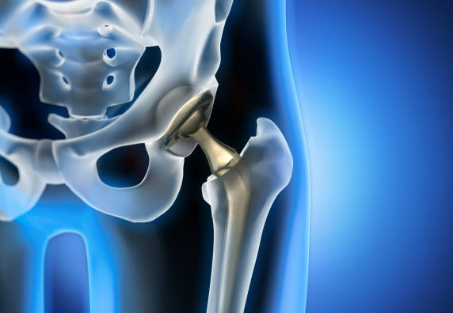

RAAC

La Récupération Amellioré Aprés Chirurgie permet une ammelioration et une anticipation de la période post opératoire